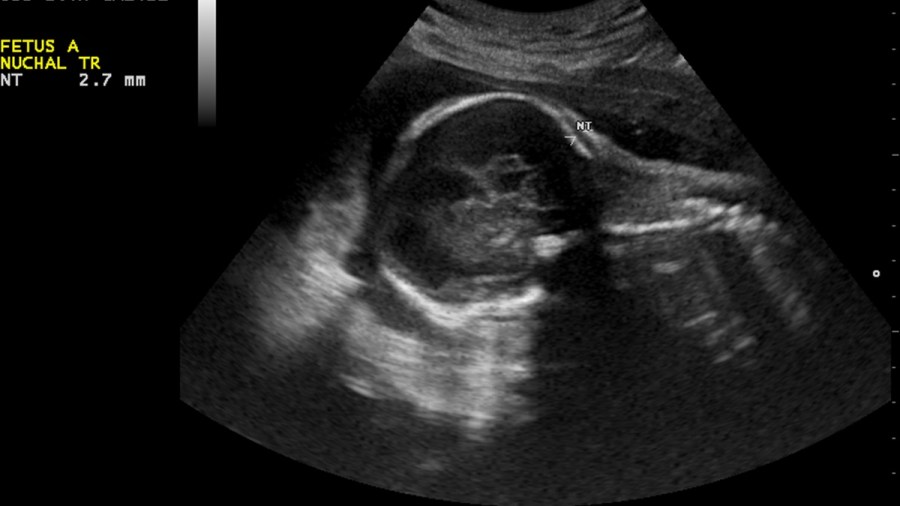

An NT scan, for those who are unaware, is a nuchal translucency screening, which can help predict chromosomal abnormalities in the child. The most common of these abnormalities is Down syndrome, which does not prevent a child from having a happy life. There are other rarer abnormalities that are potentially much worse, including some that can indicate your child will not survive through the first year. Thankfully, those situations are rare, and a positive result on an NT scan doesn’t mean that anything is definite.

1)      False positives are a possibility. The NT scan is not 100% accurate. The procedure involves measuring the nuchal fold at the base of the neck, with unusual thickness in the area indicating the possibility of an abnormality. Note the word “possibility.” There might be other reasons for unusual thickness. If a scan comes back positive, it doesn’t necessarily mean anything. From there, a more invasive test such as the CVS test will help you verify things.

Featured Image: Nevit Dilmen, CC BY-SA 3.0, cropped and resized